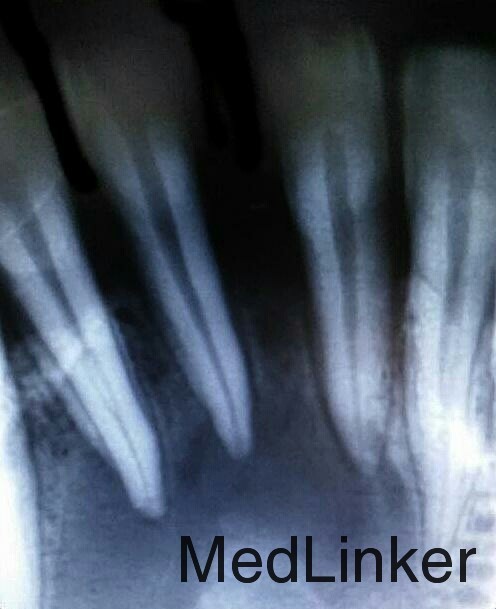

下前牙肿物

患者男,36岁,下前牙龈肿物数日,压痛红肿。

下前牙区多生牙

下颌前牙区肿物